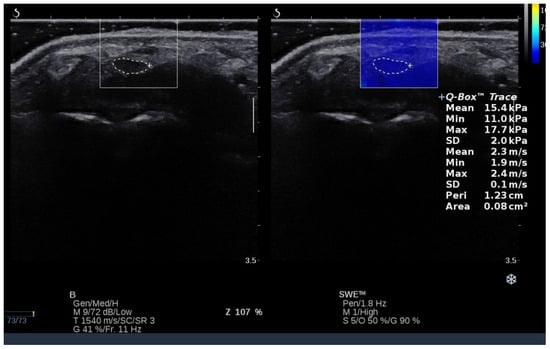

US images were collected using SWE mode, which was installed on the US machine. Images were collected in 5 different positions of both radiocarpal joints (intermediate position 0°, 45° of extension, maximum extension, 45° of flexion, and maximum flexion). To control and minimize the pressure of the head on the skin, a correspondingly large amount of hydrogel was applied to the area examined. After imaging the median nerve at the level of the carpal tunnel inlet, transverse scans were collected at each angular position (controlled with an inclinometer), starting each time with a neutral position (0°), followed by 45° of extension, maximum extension, 45° of flexion, and maximum flexion of the radiocarpal joint. Three images and then three measurements were taken at each angular position, and the average values from these measurements were used for the final analysis. For both CSA and shear modulus measurements, a contour was made of the median nerve at the inner hypoechoic border using a Q-Box Trace option implemented in the US machine (Figure 2). Both parameters were automatically calculated in the US machine and expressed in square millimeters and kilopascals (kPa) for CSA and shear modulus, respectively. CSA is related to nerve surface area, whereas shear modulus refers to the stiffness of the nerve. Higher values of shear modulus indicate higher nerve stiffness and vice versa. Detailed information about the basic physics and musculoskeletal applications of SWE is placed elsewhere [35].

Figure 2. Median nerve localization in shear wave elastography mode and measurement example of CSA and shear modulus.